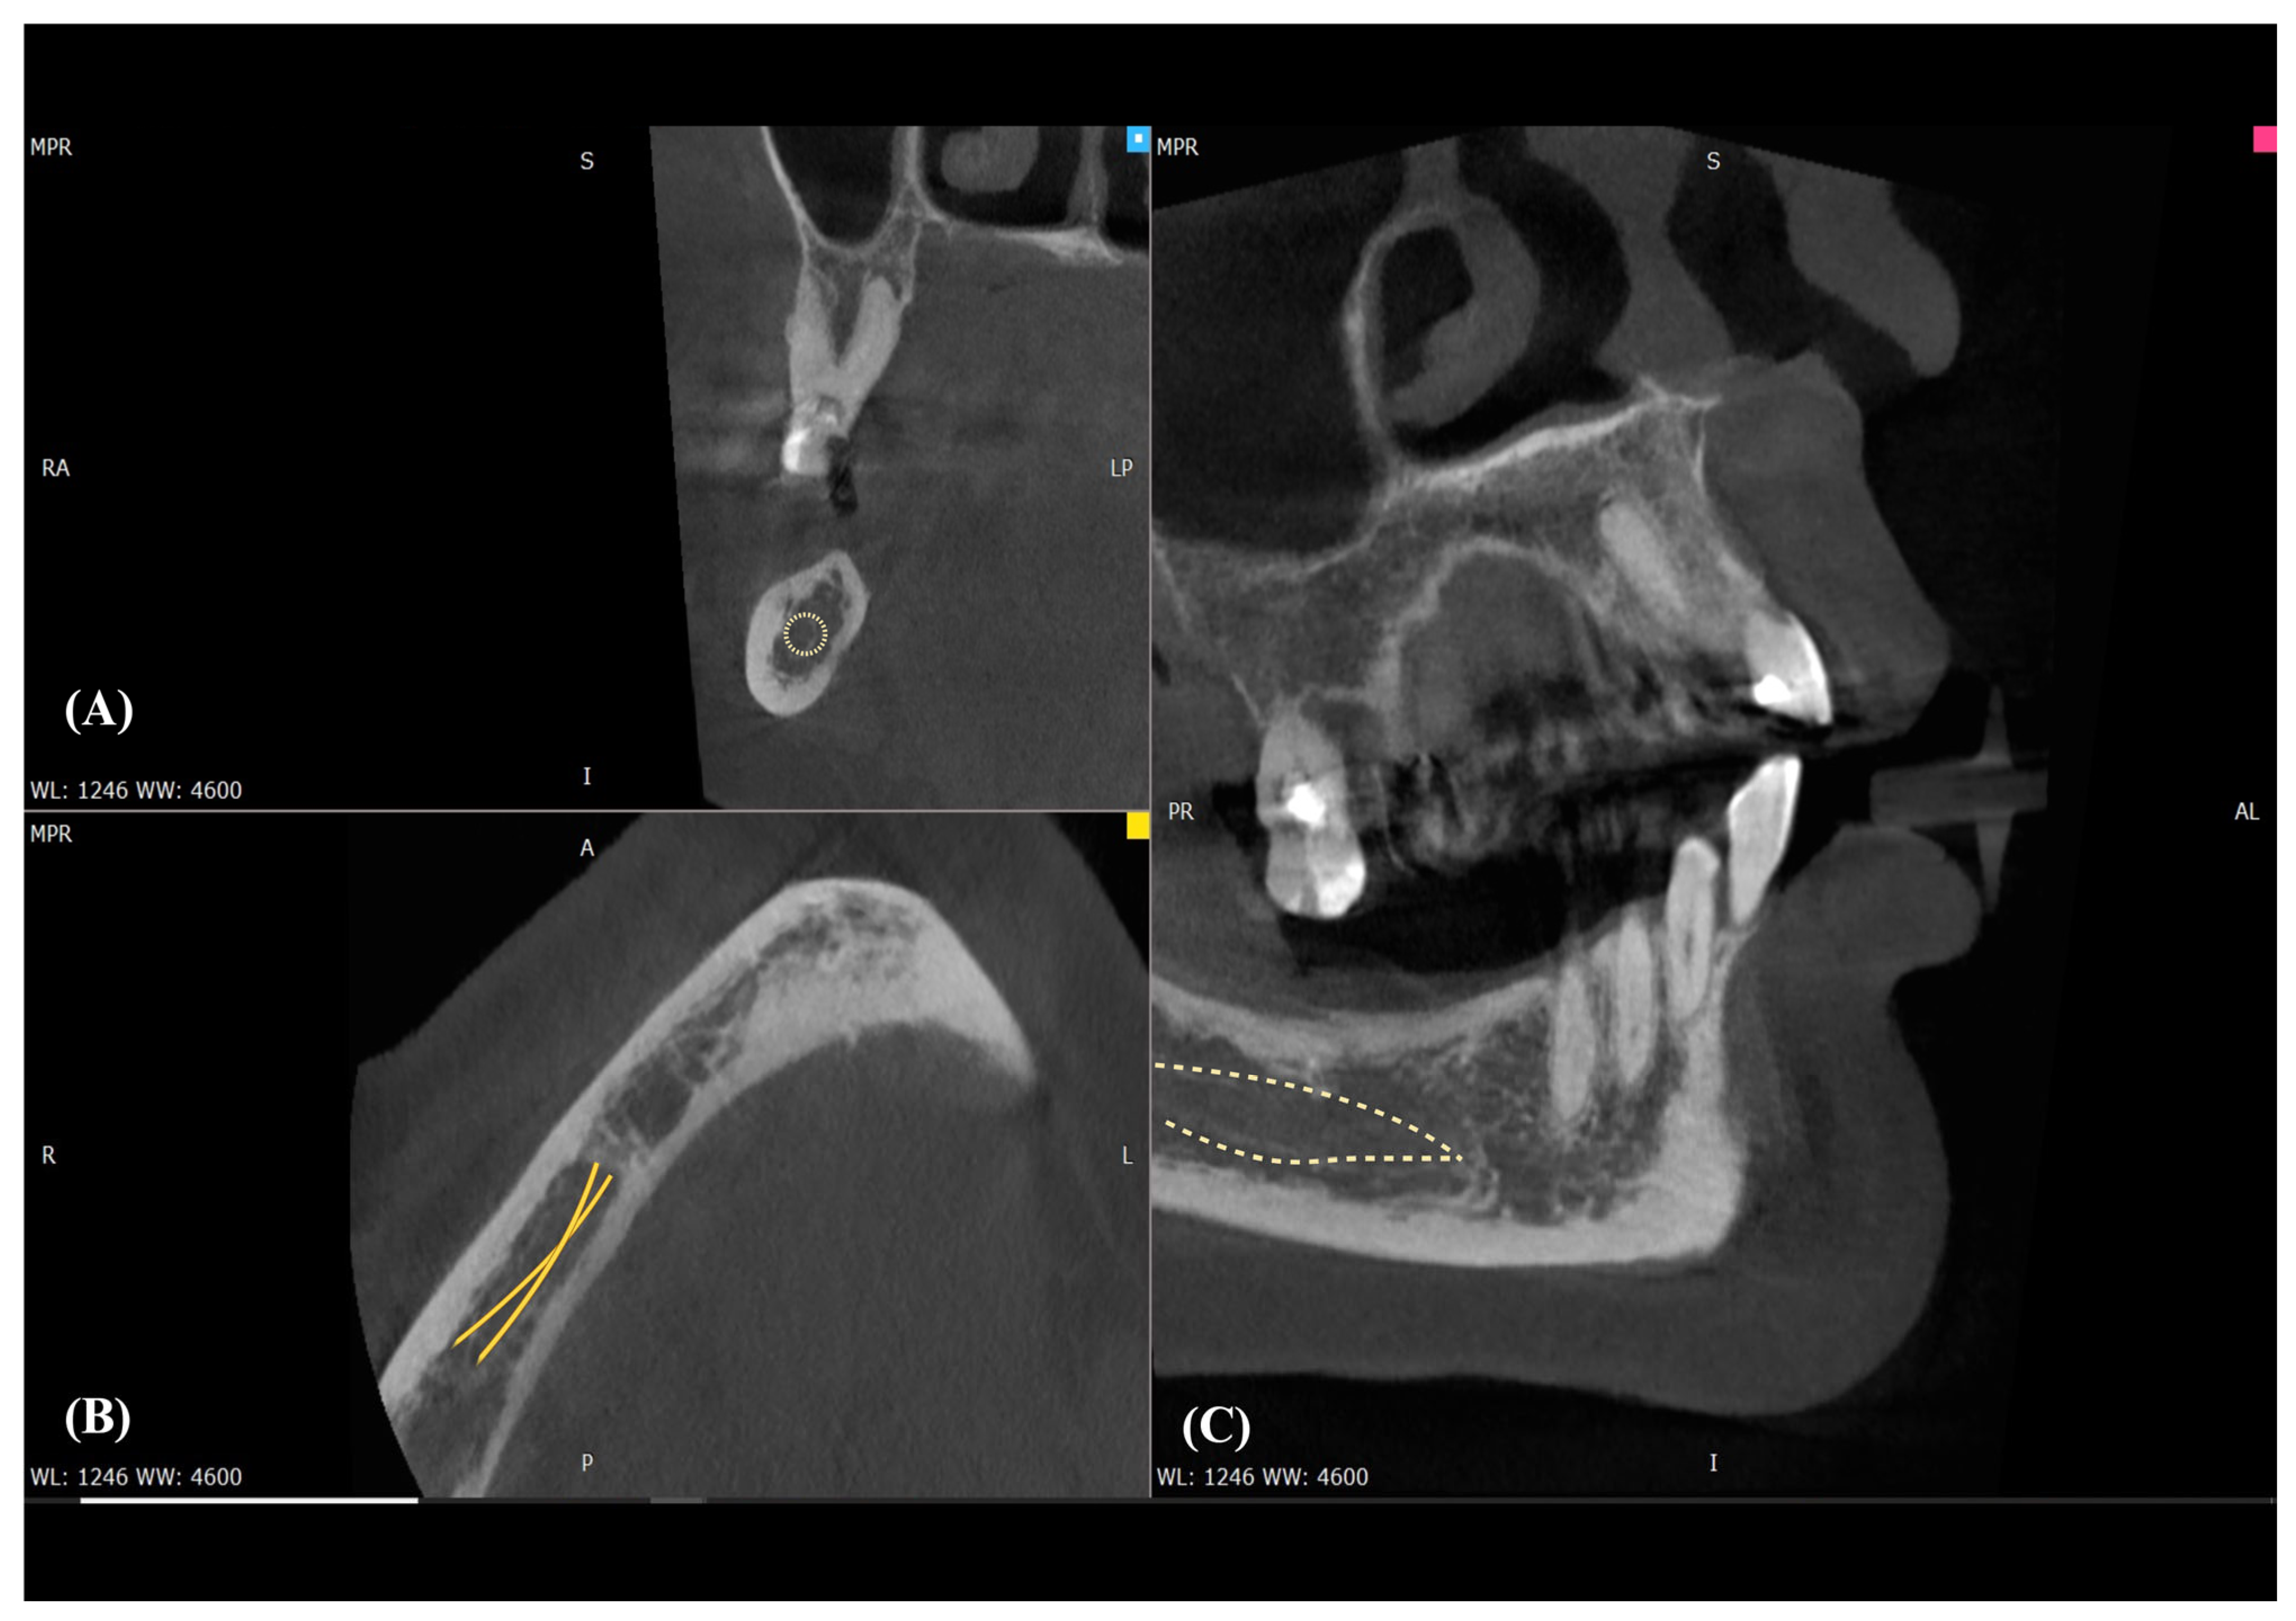

PR served as an initial screening tool. CBCT substantially increased detectability of bony variants (e.g., BMC, RMC, AMF) and enabled reproducible morphometrics (e.g., AL length). MRI at 3 T (including DTI where applicable) was used selectively to delineate the inferior alveolar neurovascular bundle in soft tissue when clinical questions extended beyond CBCT’s capability (see Table 1). Figure 2 illustrates how CBCT MPR delineates the canal course and allows direct measurement of crest–MC clearance, which PR cannot provide.

Across CBCT cohorts, BMC prevalence typically ranged from single-digit to low double-digit percentages, with extremes explained by definition and voxel size. Trifid canals were uncommon (≈1–2%). PR consistently underestimated canal branching compared with CBCT. Clinical implications for local anesthesia, osteotomy planning, and hemostasis are summarized in Table 2; study-level prevalence and definitions appear in Table 1. In practice, axial CBCT is useful for screening bifid or retromolar branches and for bilateral comparison (Figure 3).

Figure 2. CBCT multiplanar visualization of the mandibular canal (MC). (A) Axial view showing the corticated cross-section of the mandibular canal (yellow dotted circle). (B) Sagittal reconstruction demonstrating two parallel corticated tracts suggestive of a bifid configuration of the mandibular canal (yellow lines). (C) Coronal reconstruction outlining the course of the main mandibular canal within the mandibular body (yellow dotted outline).